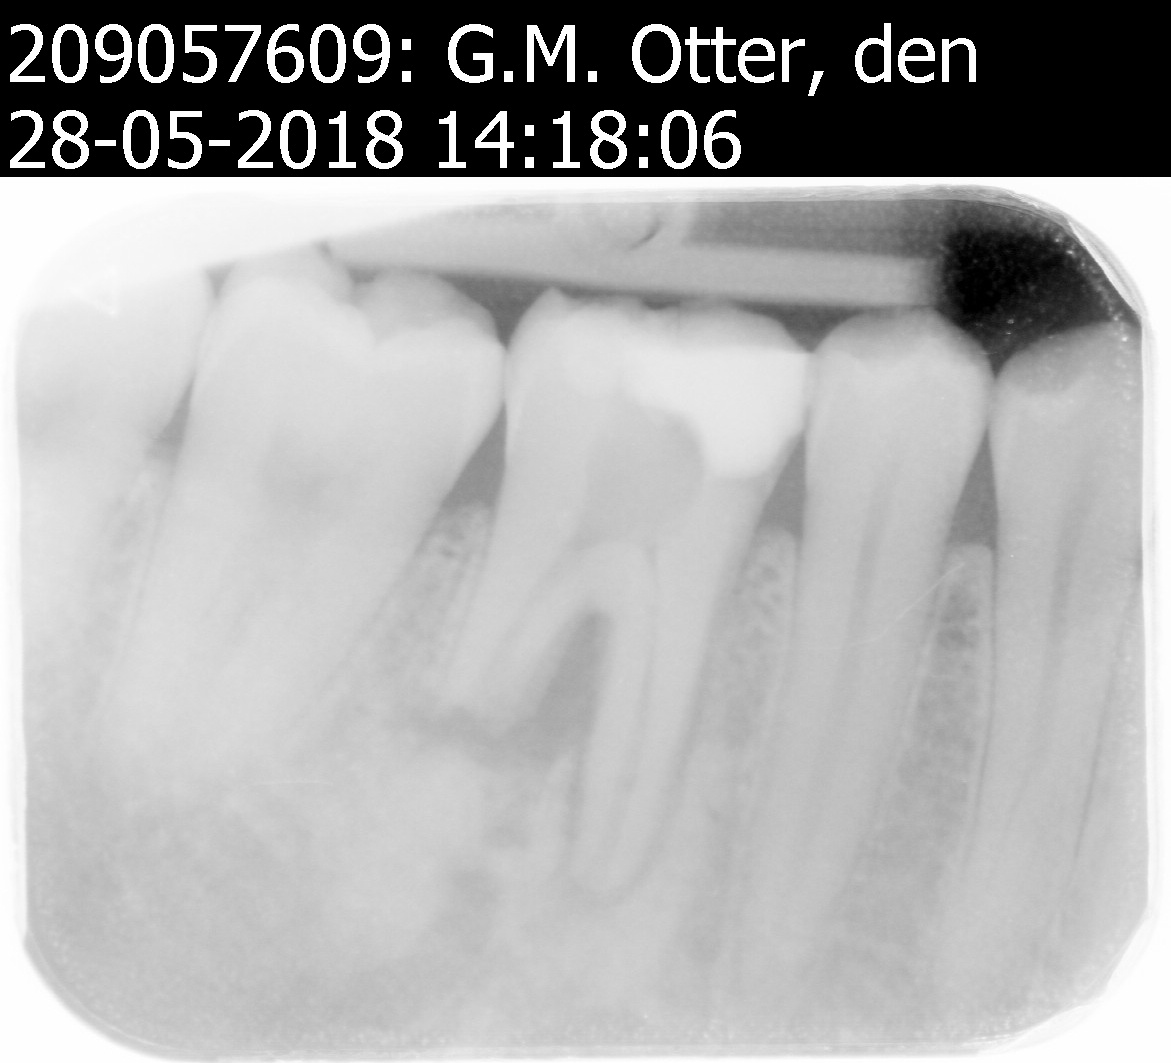

Er is bij mijn een wortelkanaal behandeling gedaan 3 maanden geleden.

Van de week geweest om het af te laten maken maar nu blijkt er een stuk wortel afgebroken te zijn.

En moet de behandeling afgemaakt worden door een endodontoloog.

ik ben even heel erg benieuwd naar de beginfoto voor ik iets zeg. Die breuk ligt namelijk op een totaal onlogische plek. Heeft in ieder geval niets te maken met de 3 maand interval, meer met de reden dat de behandeling nodig was lijkt het.

Is er in het verleden ergens sprake van een ernstig ongeval of zo?